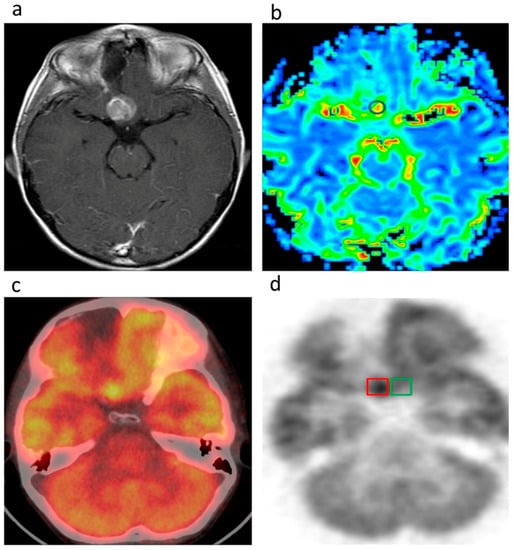

- Werner, P.; Saur, D.; Zeisig, V.; Ettrich, B.; Patt, M.; Sattler, B.; Jochimsen, T.; Lobsien, D.; Meyer, P.M.; Bergh, F.T.; et al. Simultaneous PET/MRI in stroke: A case series. J. Cereb. Blood Flow Metab. 2015, 35, 1421–1425. [Google Scholar] [CrossRef] [PubMed]

- Henriksen, O.M.; Larsen, V.A.; Muhic, A.; Hansen, A.E.; Larsson, H.B.W.; Poulsen, H.S.; Law, I. O7.08one-stop shopping in brain tumor imaging: Initial experience with PET/MR for simultaneous evaluation of tumor metabolism, structure and blood volume using 18F-fluor-ethyl-thyrosine PET and DSC-MRI. Neuro-Oncology 2014, 16, ii16–ii17. [Google Scholar] [CrossRef]